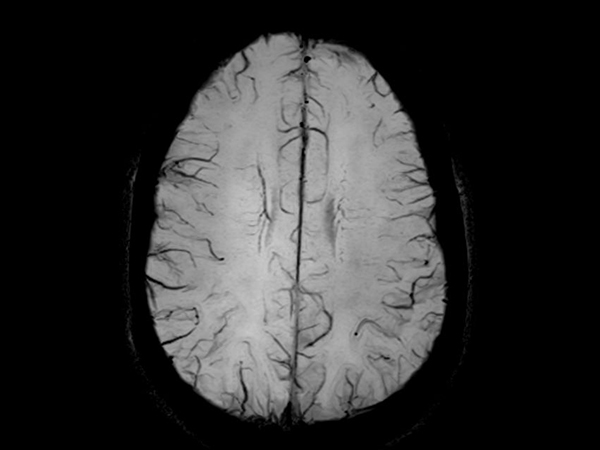

Axial SWIp (Modulus)

Axial SWIp (minIP)

Axial SWIp (Phase)